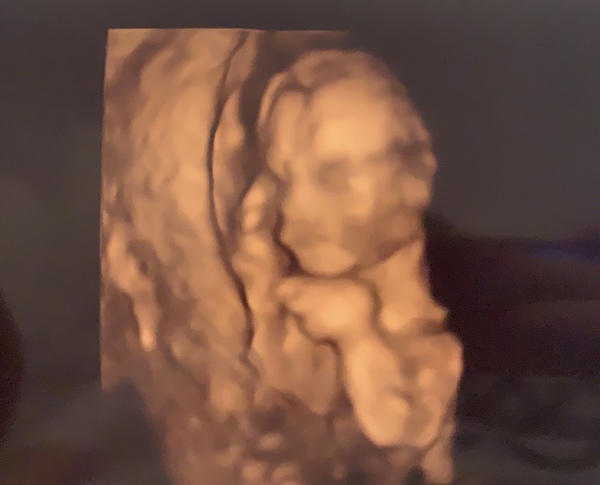

Babyhope98 · 16/06/2020 19:01

I had my gender scan today and my partner was able to attend, after the baby was being stubborn to my relief they were able to see the gender. I am having a girl as many have predicted, I think I knew deep down. Was so lovely to see her they said everything was looking perfect 🥰🥰🥰 they managed to get a 4D picture of her

@Babyhope98 aww so sweet with her little hand up by her face